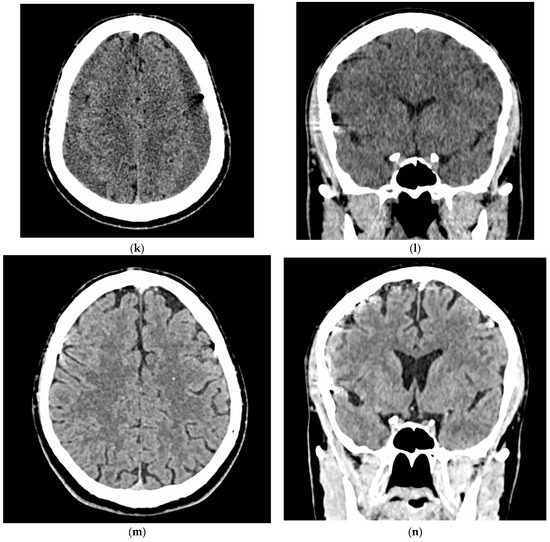

- A 70-year-old patient with left-handed CSDH and a midline shift of 12 mm, motor aphasia, and right-hand hemiparesis.

- A 42-year-old patient with bilateral CSDH that progressively increased during 1.5 months from 54 mL to 69 mL on the right-hand side and from 68 mL to 83 mL on the left-hand side, causing significant compression of both hemispheres and neurological deterioration.

- An 89-year-old patient with bilateral CSDH (no midline shift). There was no apparent connection with an antecedent head injury. However, the patient’s relatives reported that the patient did periodically fall. At the time of admission, the patient presented tetraparesis and a decreased level of consciousness.